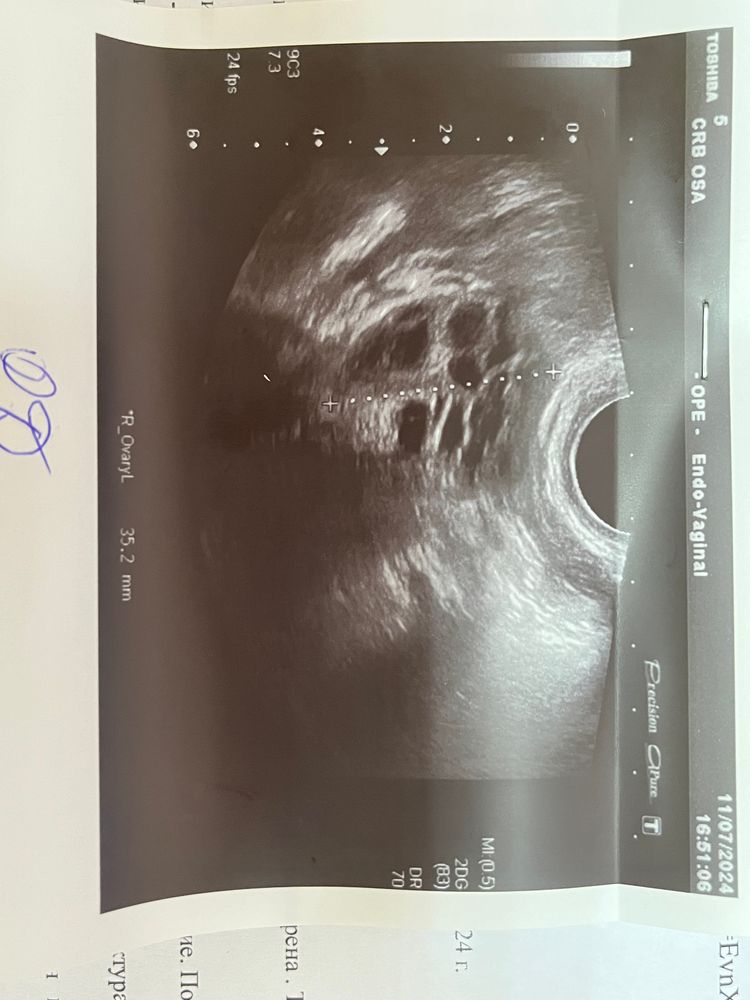

цикл 30-32 дня ПА был 12ДЦ , первый и второй тест на овуляцию это 10ДЦ, последний тест на О где полоска ярче сделан 15ДЦ, есть ли вероятность беременности тк муж уехал на заезд и в этом цикле ПА больше не будет, узи было сегодня тоже 15ДЦ, сказали что овуляции не было и доминантного фолликула нет, есть ли вероятность что овуляция уже прошла или дом.фолликул лопнул на днях или в день узи и ЖТ не успело еще сформироваться, в прошлом месяце цикл был 57 дней судя по всему тоже не было овуляции, до этого Месячные были каждый месяц, не может же быть сразу 2 цикла ановуляторных, с гормонами все в норме((( Был синдром поликистозных яичников, но 5 лет назад я забеременела при этом синдроме, значит овуляция может быть при СПКЯ

Вряд ли была О с 12 по 15 дц, тк даже если не увидели формирующееся ЖТ, то увидели бы косвенные признаки-жидкость в позадиматочном пространстве. Если циклы такие длинные, то мб О будет на 35 дц+

Если по ощущениям то была тянущая и покалывающая боль в области яичника с 12ДЦ по 15ДЦ

Базальная температура 13ДЦ - 36,5

Заключение УЗИ